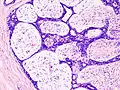

Histopathologic image of breast fibroadenoma. Core needle biopsy. H&E stain.

Fibroadenoma of the breast is a benign tumor composed of a biplastic proliferation of both stromal and epithelial components.[12][13] This biplasia can be arranged in two growth patterns: pericanalicular (stromal proliferation around epithelial structures) and intracanalicular (stromal proliferation compressing the epithelial structures into slit-like spaces).

These tumors characteristically display hypovascular stroma compared to malignant neoplasms.[2][14][9] Furthermore, the epithelial proliferation appears in a single terminal ductal unit and describes duct-like spaces surrounded by a fibroblastic stroma. The basement membrane is intact.[15]